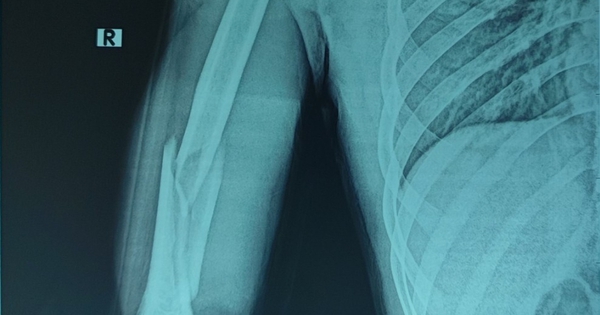

Anh C nhập viện trong tình trạng sưng đau, biến dạng, hạn chế vận động cánh tay phải. Vận động bàn ngón tay bình thường, không yếu liệt, hình ảnh X-quang cho thấy xương cánh tay phải gãy chéo vát ở 1/3 dưới có mảnh rời cánh bướm lớn.

Hình ảnh x-quang sau phẫu thuật của bệnh nhân. Ảnh: BVCC

Sau phẫu thuật kết hợp xương nẹp vít, người bệnh được chụp X-quang kiểm tra sau mổ, giải phẫu xương cánh tay được phục hồi, người bệnh ra viện sau 4 ngày.